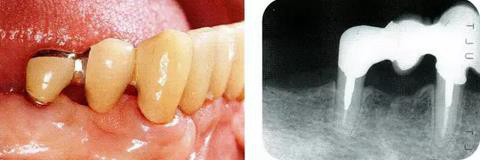

病例5  使用正畸進(jìn)行牙齒挺出,讓骨平坦化:

圖18-1(左),2 (右)▲  初診時(shí)口腔內(nèi)照片和X線片,右下4近中有較深的1壁性骨缺損,右下45有根接近。如果在這個(gè)情況下進(jìn)行骨外科處理,需要犧牲較多的右下3遠(yuǎn)中的牙槽骨。也會(huì)造成周?chē)切纬奢^大的臺(tái)階。

圖18-7(左),8(右)  佩戴最終修復(fù)體的口腔內(nèi)照片和X線片,牙槽骨平坦化,牙周袋探診2mm以內(nèi)。